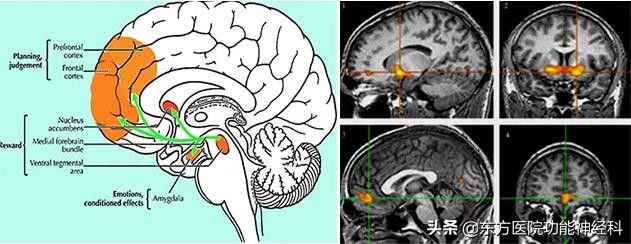

1946年美国神经外科专家Papez就提出了所谓 “情绪环路理论”,1948年他提出阻断情绪环路及联系纤维治疗精神病理论。1960年瑞典著名神经外科专家利用情绪环路理论,治疗精神分裂症49例,有效率达86%,其中26例能正常工作,且并发症少。由于现代手术损伤小,定位精确,效果好,所以现代手术治疗精神病很快取代过去额叶切除术,使精神外科进入了一个新的发展阶段。 近年功能性核磁共振成像技术的发展,为精神疾病定位研究提供了理论依据,有证据表明精神分裂症与中脑边缘系统多巴胺能神经功能异常有关:

1、VTA-NAC-ACC系统:中脑边缘多巴胺系统,中脑腹侧被盖-伏隔核-扣带回系统介导了精分的阳性症状(情感异常);

2、VTA-MPFC-DLPFC系统:中脑皮质多巴胺系统,中脑腹侧被盖-广泛前额叶皮质系统介导了精分的阴性症状(认知异常);

3、Yakovlev环路: 杏仁核为核心的与疾病的启动有关;

4、Papez环路: 海马为核心的与疾病的强化或固化有关。

(二)杏仁核环路:Yakovlev环路

1948年,Yakovlev补充了一条由额叶眶回、脑岛颞叶前区、杏仁核投射到丘脑背内侧核,又投射到额叶眶回的纤维环路,变参与情绪和行为活动的调节,称为基底外侧边缘环路。内侧环路与外侧环路共有的区域是隔区、丘脑下部和“边缘中脑区”。其中心区主管内脏活动,中间区主管情绪活动,外层区与周围环境改变活动相联系。边缘内侧环路与中脑网状结构有较多联系,这一环路被破坏将引起行为与精神活动减低,刺激将引起动作及精神活动过多综合征。因此手术破坏内侧环路可治疗运动过多综合征,而破坏外侧环路则可改善情绪异常和行为障碍。

(三) 情感环路、犒赏环路

(三)伏隔核的功能:奖赏环路

中脑边缘多巴胺系统被认为是奖赏效应的神经基础,伏隔核在奖赏效应中的作用很早就被人们所重视。支持伏隔核在奖赏效应中作用的最直接证据是动物自我给予多巴胺类似物(即直接用多巴胺受体激动剂)或增加细胞外多巴胺的药物。这些奖赏物质可作为强化剂使动物不断地重复某种行为以获得奖赏或欣快的感觉。 有研究者记录了猴子接受奖赏时中脑边缘系统多巴胺神经元的放电活动。当在猴子面前展现一个促进食欲的食物。如水果汁,多巴胺神经元会出现一个短时程的放电活动。如果奖赏与视听刺激多次结合,多巴胶神经元活动的时程会改变,放电出现的时间从奖赏投递后转变为奖赏刚一出现时,多巴胺神经元活动的转变类似动物对有欲望刺激的反应从非条件反射向条件反射转变。伏隔核多巴胺不仅在介导自然奖赏(水、食物)的即刻快乐方面是重要的,而且介导预示即将发生奖赏的唤醒效应。当然在奖赏回路中处多巴胺外还有其他的递质,如阿片肽等参与。